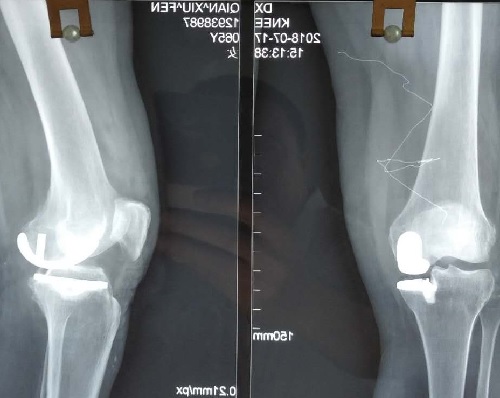

患者钱某,女性,65岁,自诉因右膝疼痛3年有余,近期活动障碍,严重影响日常生活。在辗转多家医院就诊后,入住我院骨五科进行治疗。入院检查后,主治医生敖日格勒诊断为“右膝内侧室间病变”。医者仁心,本着对每位患者健康负责的宗旨,骨五科医疗团队针对患者病例进行反复讨论,制定最佳的诊疗方案,在征得患者知情同意后,决定为患者行膝关节骨关节炎单髁置换术。手术由胡中申主任亲自主刀,在充分的术前准备及手麻科医生的密切配合下,手术顺利成功完成。术后,患者康复状况良好,膝关节屈伸功能恢复,已可扶拉行器下地行走。钱阿姨及家人对于手术效果非常满意,她兴奋地说:“我现在最大的感受就是疼痛明显减轻了,关键是术后第二天我就可以下地走路了,医生和护士对我都非常好,一直耐心地指导我如何更好锻炼和康复,这样精湛的技术和暖心的服务,市医院的技术确实牛,必须为你们点赞! ”

据悉,单髁手术是应用微创外科(Minimally Invasive Surgery, MIS)技术。该技术与全膝关节置换术比较,单髁置换手术创伤小,可较好地保留正常的骨量、交叉韧带和正常侧的半月板。同时,手术时间短、康复快、住院时间短、失血量少、费用低及严重并发症少,术后关节功能恢复更接近生理状态。由于该手术具有创伤小、恢复快的优良特点,成为膝关节骨性关节炎患者的福音。